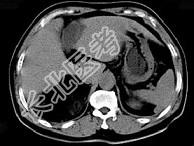

- 单项选择题男,59岁, 右侧腰背酸痛,CT检查如图所示, 应诊断为 ( )

A、右肾上腺腺瘤

B、右肾上腺转移瘤

C、右肾上腺髓样脂肪瘤

D、右腹膜后脂肪瘤

E、右肾血管平滑肌脂肪瘤